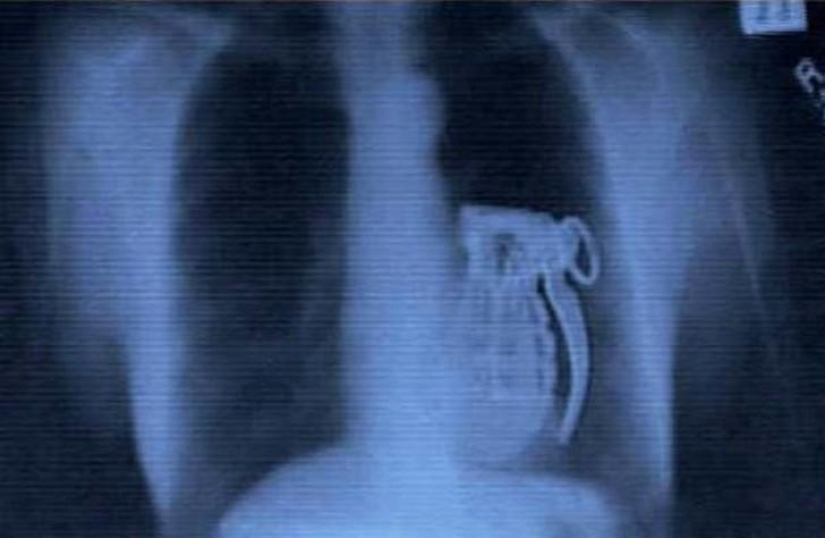

Grenade.